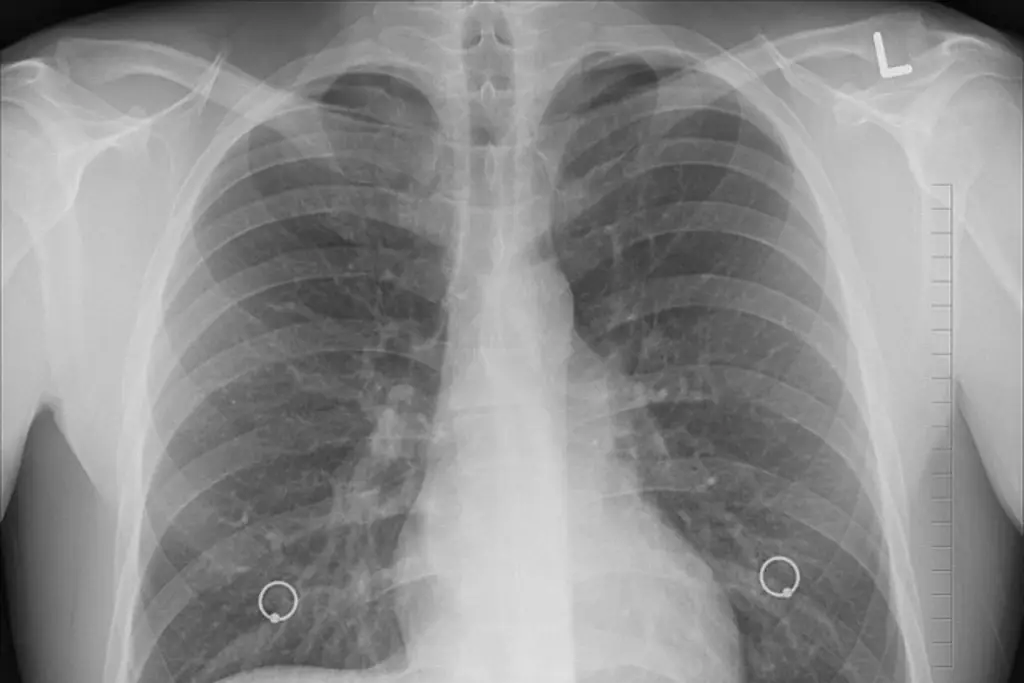

Diagnóstico temprano del cáncer de pulmón sube considerablemente la supervivencia: experta

La supervivencia al cáncer de pulmón, principal causa de muerte oncológica en hombres y la segunda en mujeres, se eleva del 23 % al 60 % con un diagnóstico temprano, explicó este viernes una especialista en un seminario celebrado en la capital peruana.

El cáncer de pulmón provocó en 2022 más de 2,48 millones de nuevos casos y 1,81 millones de muertes en el mundo, de acuerdo con la Agencia Internacional para la Investigación en Cáncer (IARC, OMS), una cifra que representa el 12,4 % de todos los diagnósticos de cáncer y el 18,7 % de las muertes oncológicas globales.